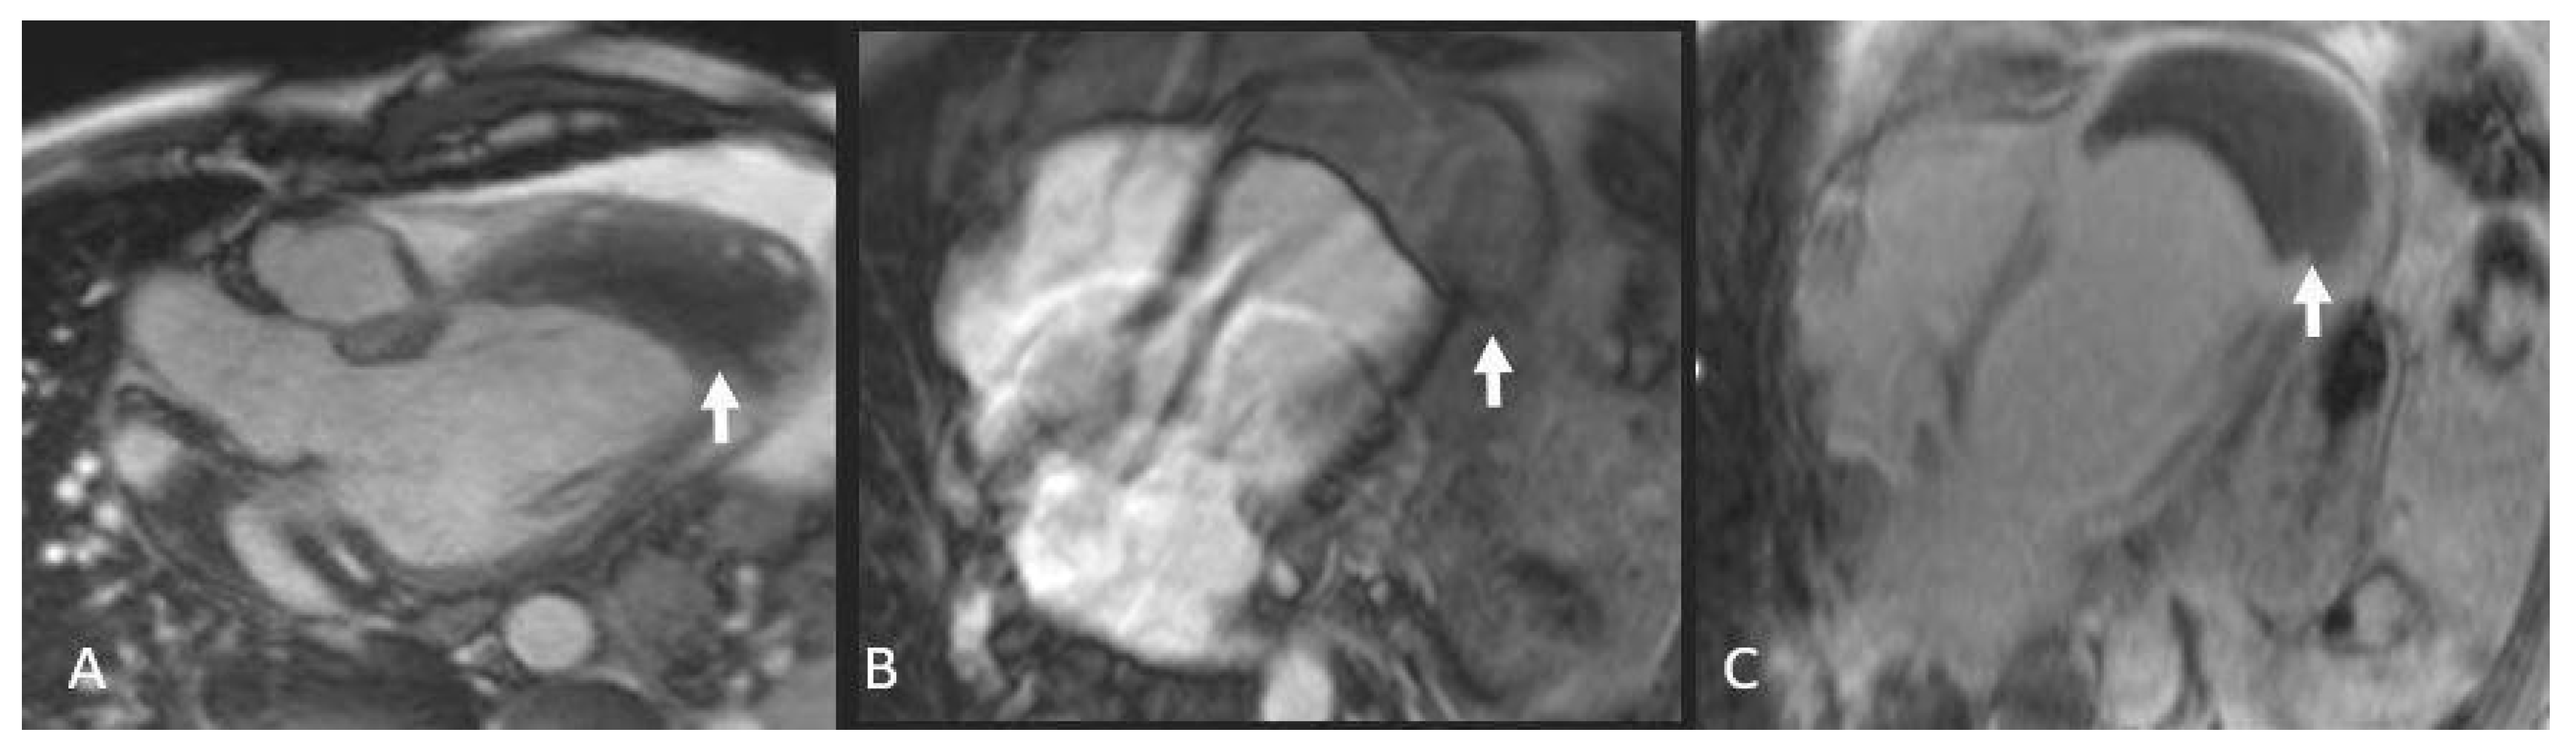

5.4. Fibroelastoma

Papillary fibroelastoma (Figure 9), though an uncommon primary cardiac neoplasm overall, is the most frequent valvular tumor—comprising about 75 % of such lesions—and shows a clear male predominance; histologically it forms delicate papillary fronds built on a fibrous core surrounded by loose connective tissue, occasionally interspersed with elastic fibers, all sheathed by a single layer of hypertrophied endothelium. Approximately 80% of fibroelastomas are found in the aortic or mitral valves, with rarer occurrences in the tricuspid or pulmonary valves and even rarer involvement of the mitral chordae tendineae [3].

On CT, fibroelastomas appear as small hypodense masses with irregular margins. On MRI, they present as well-defined, pedunculated masses of about 1.5 cm, showing an iso-hyperintense signal in T1 and T2 sequences and may exhibit mobility in CINE sequences. The characteristic appearance on echocardiogram is similar to a sea anemone. Its location can lead to the formation of thrombotic endocarditis components [22,42].

Figure 9. Fibroelastoma: MRI images Steady State T2 in 3 and 4 chamber projection (A and B) and LGE (C) show a small polypoid formation adhered to the mitral valve.